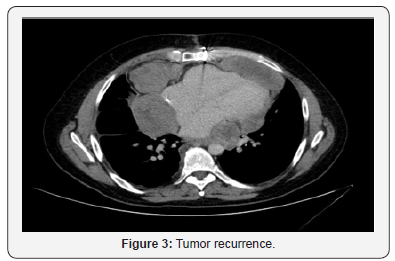

40-year-old man visited our Hospital in June 2014 due to chest pain. The physical examination had no abnormal findings. After admission, the chest X-ray indicated cardiomegaly and echocardiography showed dates of pericardial effusion. The patient received treatment and was discharged from hospital after one week with pericarditis diagnosis. Four months later, he started with similar symptoms and echocardiography showed massive pericardial effusion with a tumorous region in the pericardial space. Echocardiography showed a big mass with compression of right cavities without stenosis, gradient valve tricuspid of 3,7mmHg. The chest CT, as well as confirming the effusion, revealed a pericardial cystic mass with pericardial thickening (Figure 1). Is suggested of neoplasm like mesothelioma or sarcoma. Pericardiocentesis was performed and 1000 mL of mpericardial fluid was drained. According to these findings, surgical resection through pericardiectomy with median sternotomy was performed on October 2014 with pathology study. The tumor was in the pericardial space, with irregular morphology, size of 14×5.7x6 cm and 1500mL serohematic pericardial fluid. Histological analysis showed spindle cells-type sarcoma, necrosis and 18 mytosis. Immunohistochemical analysis showed that the tumor cells were positive for bcl-2, CD99, vimentin and the Ki-67 proliferative index was 50%; however, staining for S100 proteins, CD34, CK AE1/AE3, EMA, enolasa, musclespecific actin (HHF35) and desmin was negative. On the other hand, fluorescence in situ hybridization revealed a moderate prevalence (64%) of cells with interruption of the SYT gene (18q11.2). Final diagnosis was monophasic synovial sarcoma with poorly differentiated areas with unspecified margins. Patient had a good clinical evolution but the control CT scan three months later, showed tumor persistence, 7.5x11x2.8cm with compression in right ventricle. The tumor grew from the inner surface of the pericardium near the origin of the pulmonary artery and ascending aorta with invasion of left atrium and right coronary. The study was completed with angiography scan. The case was evaluated in multidisciplinary committee. The specialist decided re-intervention, but complete resection was not possible because of the proximity and attachment to the great vessels. In CT scan after surgery, the mass was reduced around 50%. In multidisciplinary committee, we discussed the possibility of adjuvant radiation therapy. Finally, patient received radiation treatment with prescription dose of 45Gy, 1.8Gy daily (Figure 2). He didn´t had any toxicity. After three months, patient had a new recurrence. In committee we decided not surgery, patient received chemotherapy. Finally, patient had a new recurrence and died in 12 months after diagnosis (Figure 3).